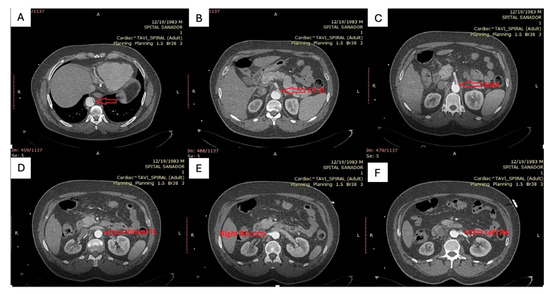

| True lumen | Severely compressed along descending thoracic and abdominal aorta | Re-expanded across thoracic segment | Stable re-expansion |

| Visceral perfusion | SMA and celiac from severely collapsed TL; R renal from FL | TL restored at visceral segment; R renal improved inflow | Full visceral patency; no endoleak |